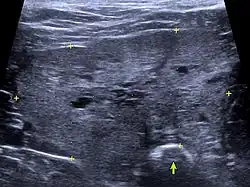

Klinisches Bild und die die Rektaluntersuchung der Prostata sind bereits stark hinweisend auf die BPH. Die Prostata ist in der Regel symmetrisch vergrößert und die mediane Furche zwischen den beiden Lappen des Prostatakörpers bleibt erhalten. Weitere Befunde liefert die Sonografie. Die Drüse ist vergrößert, das Parenchym gleichmäßig echoreich (hyperechogen). Gelegentlich treten Prostatazysten auf, die sich als runde, dünnwandige anechogene Gebilde darstellen. Röntgenologisch kann die Größe der Prostata bestimmt werden, gegebenenfalls auch Verkalkungen oder Lymphknotenvergrößerungen. Differentialdiagnostisch sind vor allem die akute und die chronische Prostatitis in Betracht zu ziehen. Diese Erkrankungen lassen sich mit den derzeitigen Methoden nicht sicher von der BPH abgrenzen. Weiterführende Untersuchungsmöglichkeiten sind Elastographie, Computertomographie (insbesondere mit Kontrastmittel) und Magnetresonanztomographie. Diese Untersuchungen sind jedoch nur in Tierkliniken möglich, erfordern eine Vollnarkose und sollten daher vor allem bei Verdacht auf Prostatakrebs durchgeführt werden.